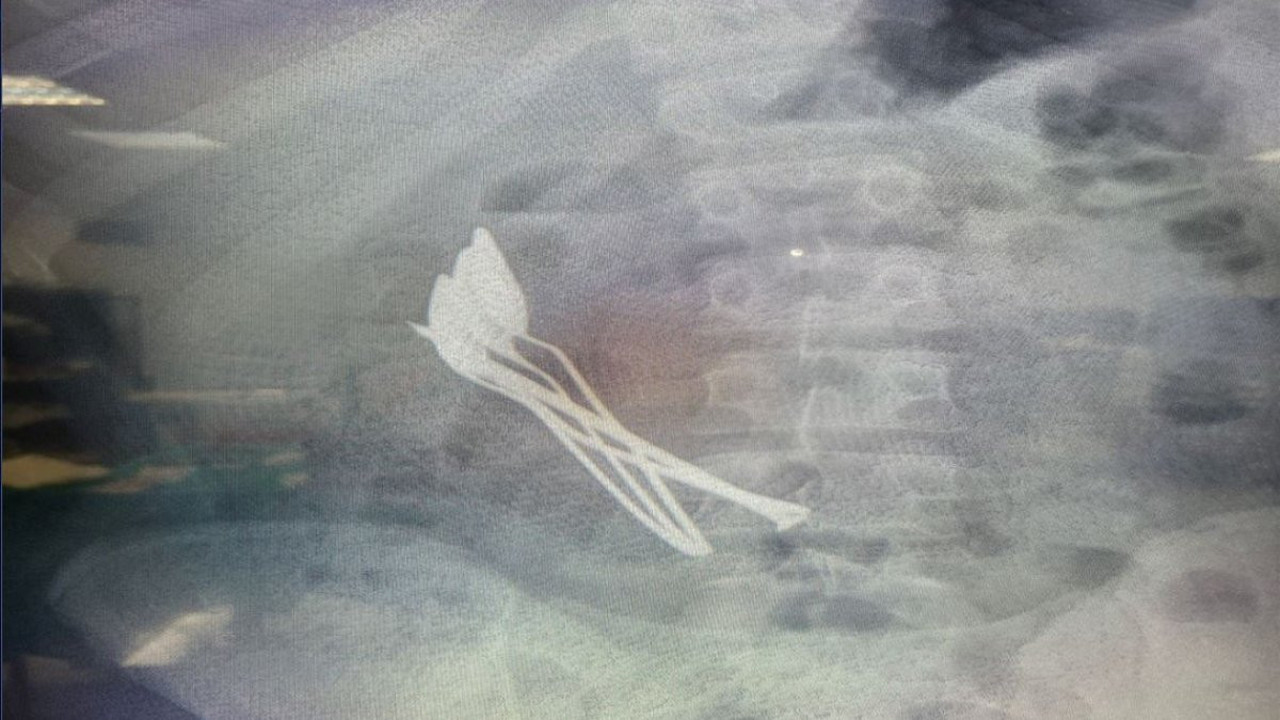

Şehirde, bir aile çocuklarının mide şikayeti sonrası hastaneye başvurdu. Kayseri Şehir Hastanesi’nde yapılan incelemede çocuğun midesinde 4 metal tatlı kaşığı ve 1 çivi görüldü.

Kayseri Şehir Hastanesi Çocuk Cerrahisi ve Ürolojisi Anabilim Dalı Başkanı Doç. Dr. Mustafa Erman Dörterler ve ekibi tarafından yaklaşık 2 saat süren operasyonda çocuğun midesindeki kaşıklar ve çivi çıkarıldı. Erkek çocuğu tedavi sonrası taburcu edildi.